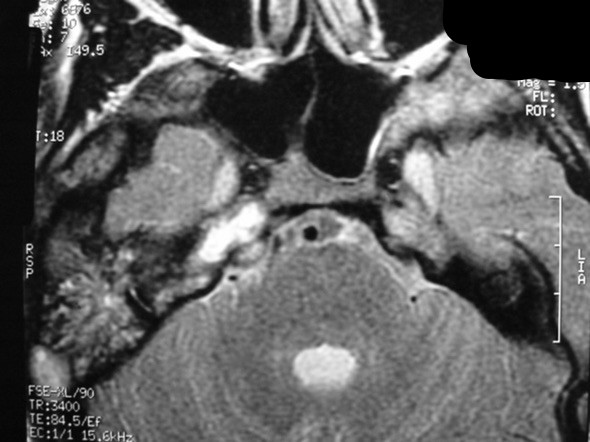

The petrous apex is a relatively inaccessible area that can occasionally harbor serious disease. Disease processes that usually cause symptoms are typically inflammatory or neoplastic in nature. Petrous apex lesions typically cause nonspecific symptoms such as headache, but as the lesion becomes more extensive, adjacent structures such as cranial nerves can become involved. A common early and specific sign of a petrous apex process is abducens palsy. Current imaging techniques can usually provide enough supplemental information to allow a focused plan of treatment. It is important to determine whether a petrous apex lesion can be observed or, if surgical treatment is required, whether a drainage or excision is required. There are various available surgical approaches to the petrous apex. The choice depends on the status of hearing function as well as the suspected pathology, which will dictate whether a drainage or excisional procedure is required.

- Summarize the types of pathology that can occur in the petrous apex, the imaging required, and proper interpretation of information so that a proper differential diagnosis can be formulated.